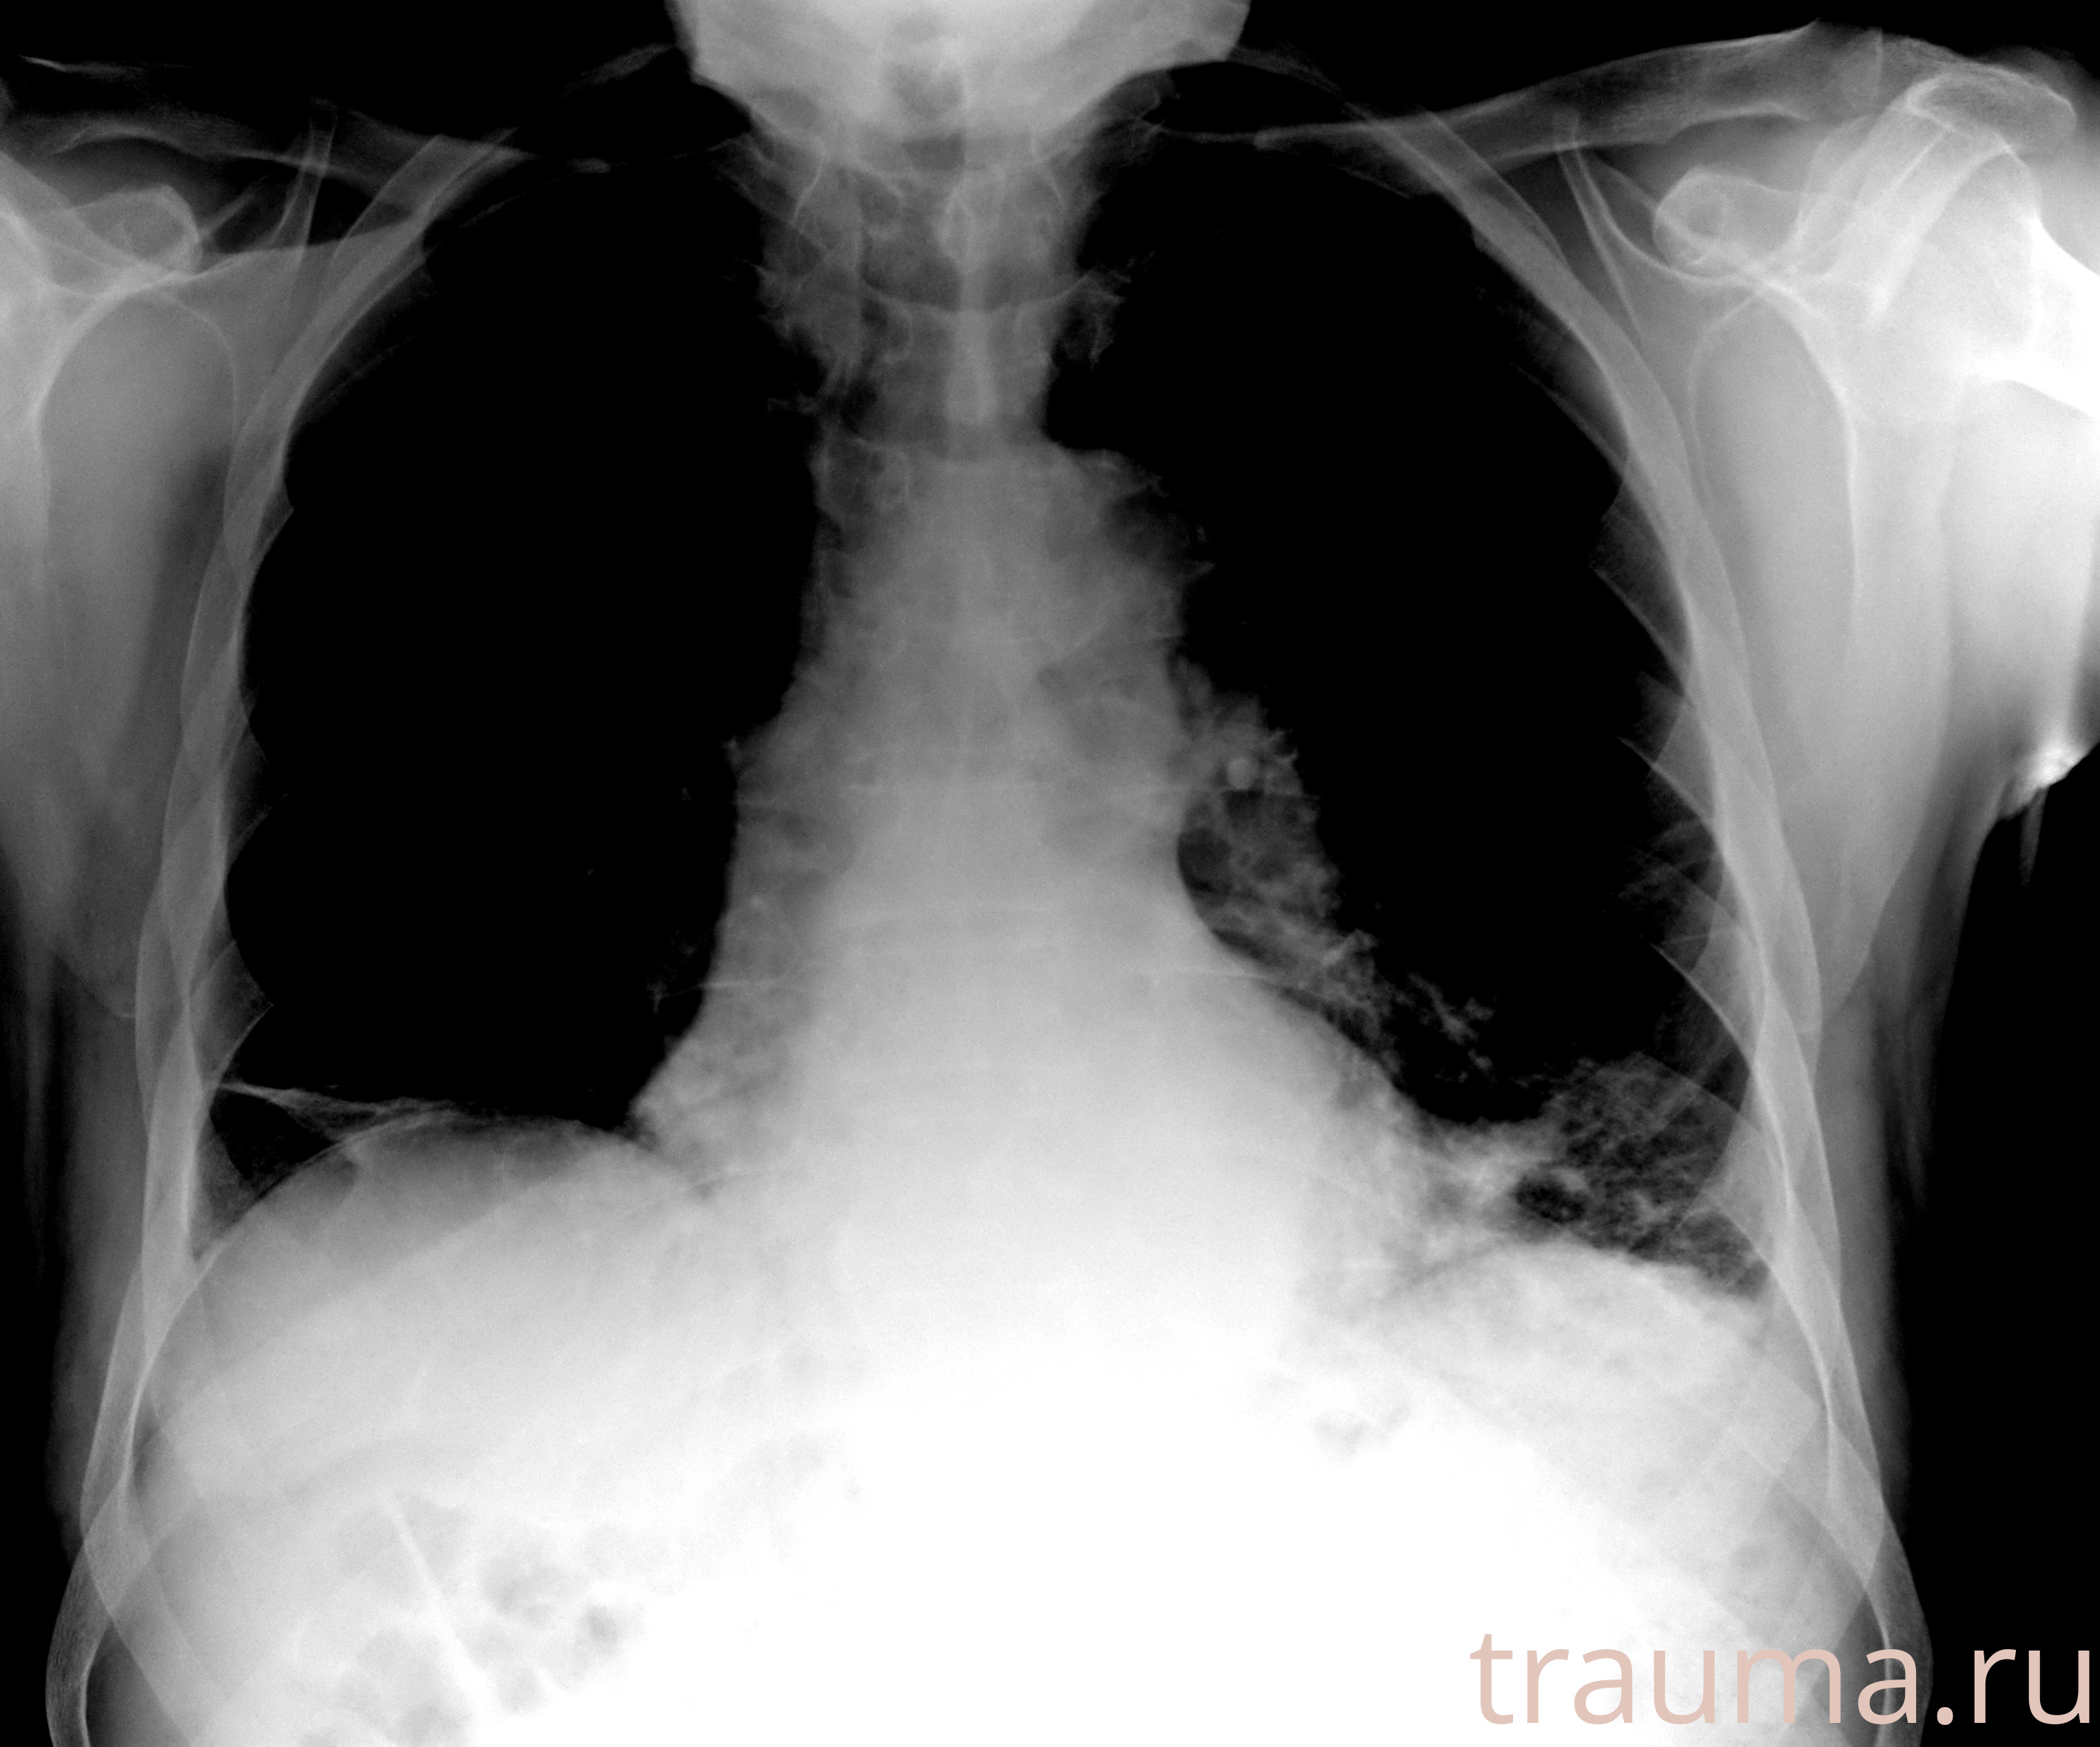

Рентгенограммы

Рентген на дому: по вашему адресу приезжает врач-рентгенолог, травматолог-ортопед с мобильным рентгеновским аппаратом, проводит диагностику травмы или заболевания, делает необходимые рентгенограммы, дает рекомендации по дальнейшему лечению. Получить качественные снимки в домашних условиях возможно благодаря уникальной методике, разработанной МосРентген Центром для института  Склифосовского